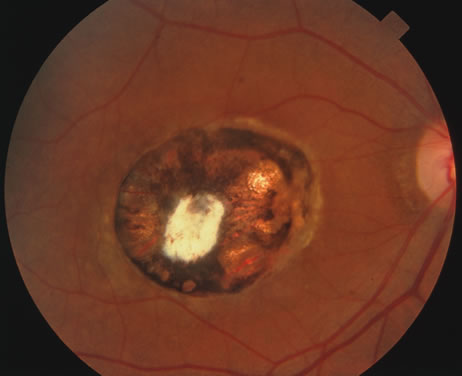

The acute retinal necrosis (ARN) syndrome is most often caused by the herpes zoster virus, although occasionally it may be a result of herpes simplex infection.12 It is typically described in healthy patients although association with immunosuppressed patients has also been described. Granular, nonhemorrhagic areas of retinal necrosis may be observed in the fundus, often rapidly coalescing with resulting blindness often caused by retinal detachment. There is often an associated vasculitis and vitritis. In immunocompromised patients VZV or HSV retinitis may also take the pattern of progressive outer retinal necrosis (PORN) (Fig. 6). PORN differs from ARN in that the former is multifocal, localized to the outer retina, and is less often associated with vasculitis and vitritis.

Fig. 6. Fundus lesions of progressive outer retinal necrosis (PORN). Note the multifocal lesions.